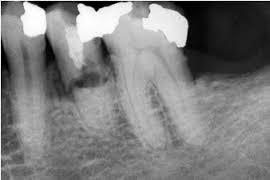

Răng sâu    Răng nha chu trầm trọng   Răng bị nhiễm trùng

Răng mọc lệch   Răng chỉnh hình             Răng bị chấn thương

Bác sĩ tiến hành thăm khám tổng quát sức khỏe răng miệng, chụp phim X-quang quanh chóp hoặc X-quang toàn hàm (nếu cần thiết) ghi nhận đặc điểm, hình dạng của những răng cần nhổ và các răng xung quanh.

X- Quang quanh chóp   X- Quang toàn hàm

Từ đó, bác sĩ nhận định được mức độ khó dễ của ca tiểu phẫu. Điều này đặc biệt quan trọng đối với các ca nhổ răng khôn.